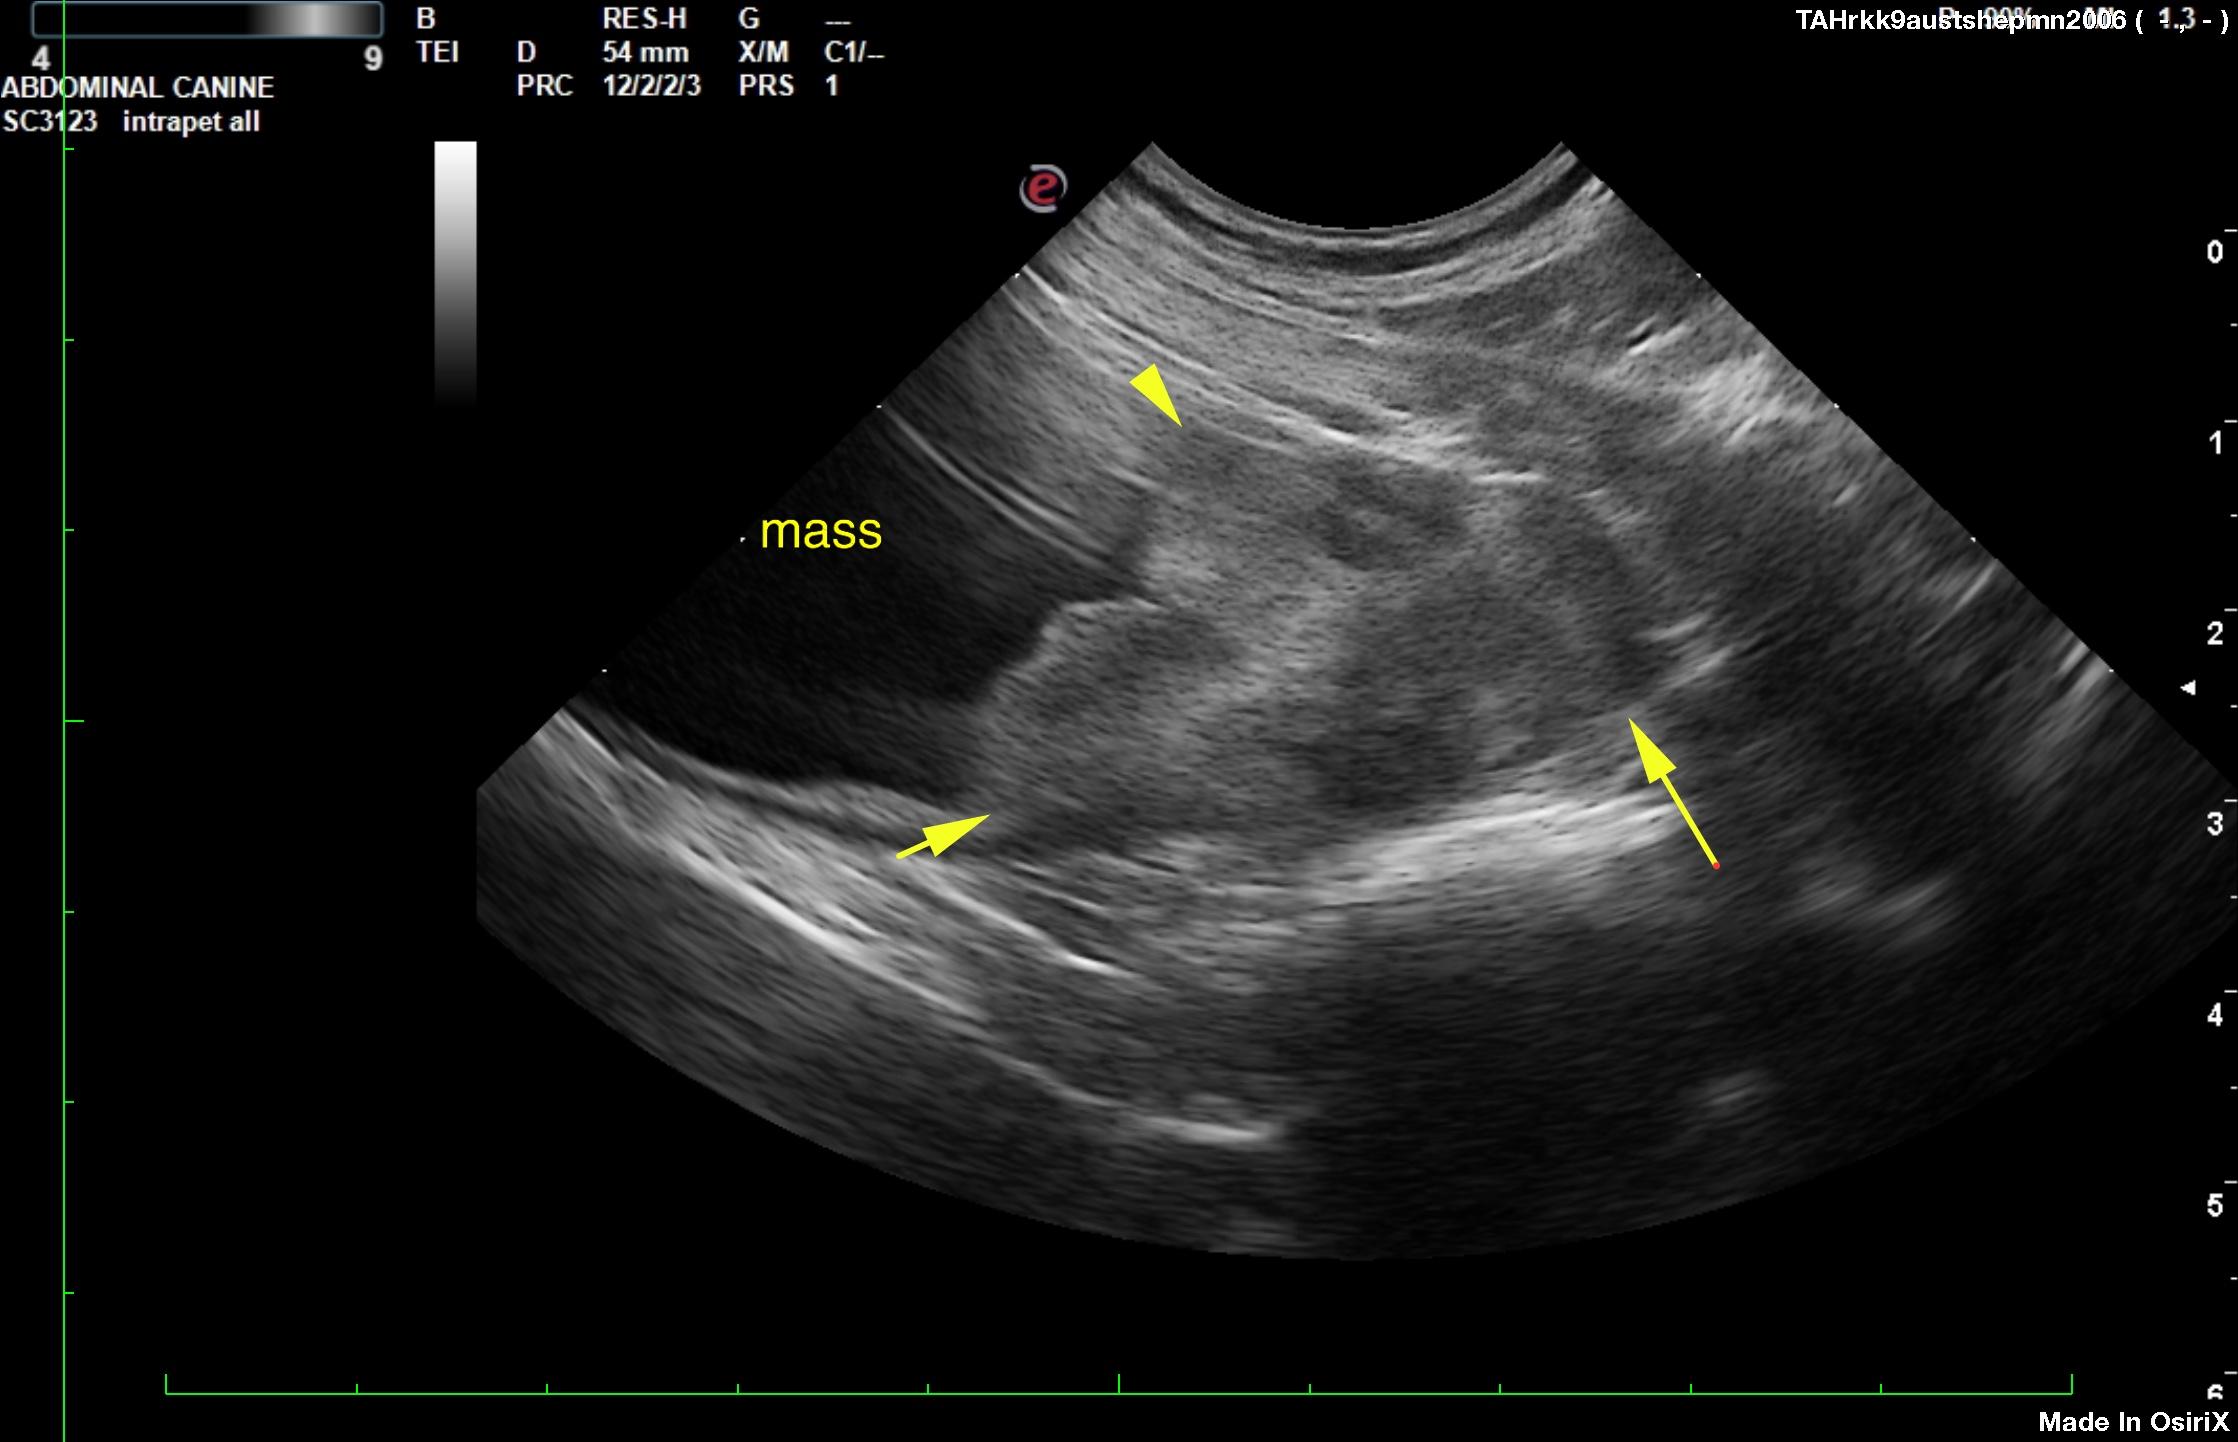

An 11-year-old MN Australian shepherd was presented for evaluation of progressive polyuria and stranguria. Urinalysis showed abnormal epithelial cells. On survey radiographs, mineralization near the pelvis in area of bladder was evident.

An 11-year-old MN Australian shepherd was presented for evaluation of progressive polyuria and stranguria. Urinalysis showed abnormal epithelial cells. On survey radiographs, mineralization near the pelvis in area of bladder was evident.